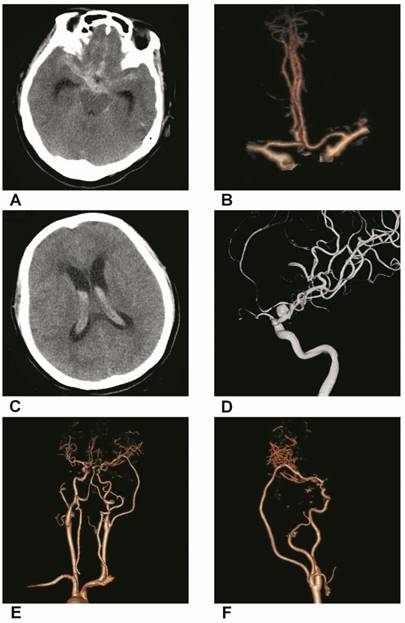

At our institute, we prefer to perform the direct clipping operation because it is convenient and often results in a good outcome; a typical case is shown in Figure 2. In addition, profile visualized intraluminal support (LVIS) stents are a good choice due to the 12-21% surface area coverage [83], though double LVIS stents are sometimes necessary. The trapping with bypass method is still used as the last resort and is effective; a typical case is shown in Figure 3.

Figure 3

Trapping with bypass of BBAs of the supraclinoid ICA. A, CT of the first SAH showing the hemorrhage in the suprasellar cistern. B, CTA showing a small BBA of the supraclinoid ICA. C, CT of the second SAH showing the intraventrical hemorrhage. D, DSA showing the BBA became bigger. E-F, Postoperative CTA showing that the BBA was trapped with EC-middle artery bypass.